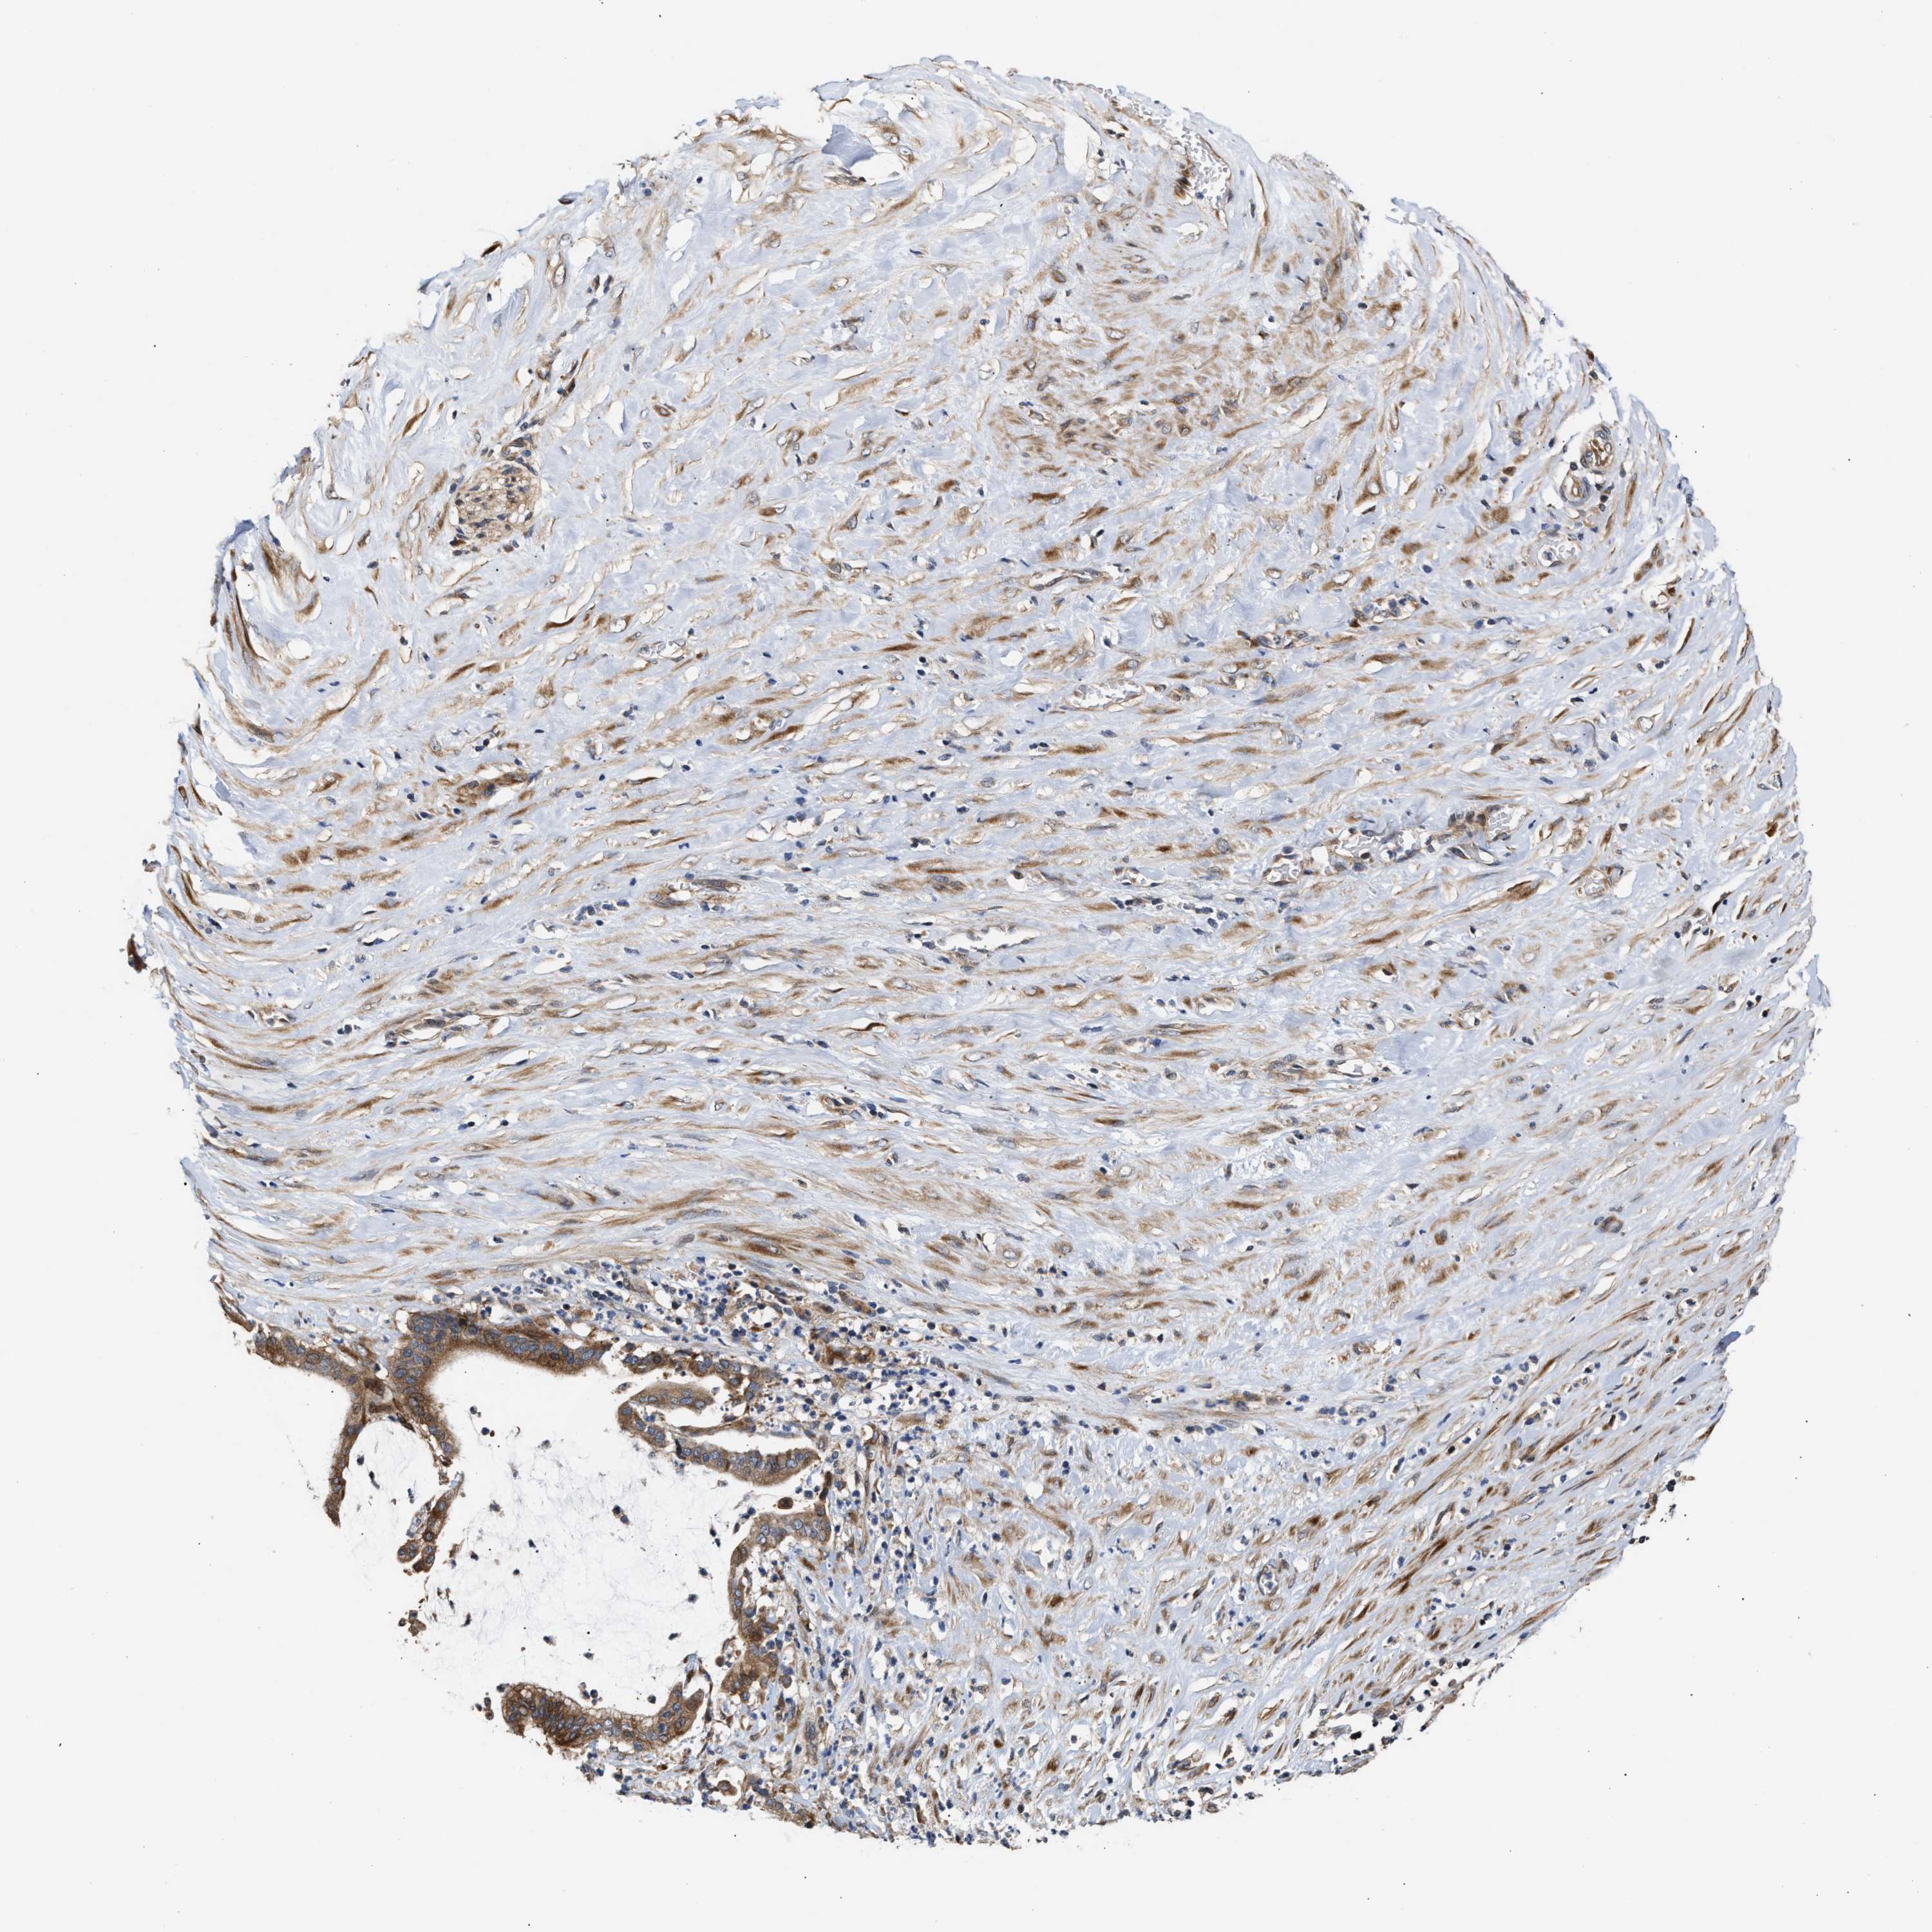

PANCREATIC CANCER - Protein expressioni

A mouse-over function shows sample information and annotation data. Click on an image to view it in a full screen mode. Samples can be filtered based on level of antibody staining by selecting one or several of the following categories: high, medium, low and not detected. The assay and annotation is described here.

Note that samples used for immunohistochemistry by the Human Protein Atlas do not correspond to samples in the TCGA dataset.

Antibody stainingi

Antibody staining in the annotated cell types in the current human tissue is reported as not detected, low, medium, or high, based on conventional immunohistochemistry profiling in selected tissues. This score is based on the combination of the staining intensity and fraction of stained cells.

Each image is clickable and will lead to virtual microscopy that enables deeper exploration of all samples and also displays staining intensity scores, fraction scores and subcellular localization as well as patient and tissue information for each sample.

Antibody HPA020430

Antibody CAB020767

Staining

High

Medium

Low

Not detected

Intensity

Strong

Moderate

Weak

Negative

Quantity

>75%

75%-25%

<25%

None

Location

Nuclear

Cytoplasmic/membranous

Cytoplasmic/membranous,nuclear

Adenocarcinoma, NOS